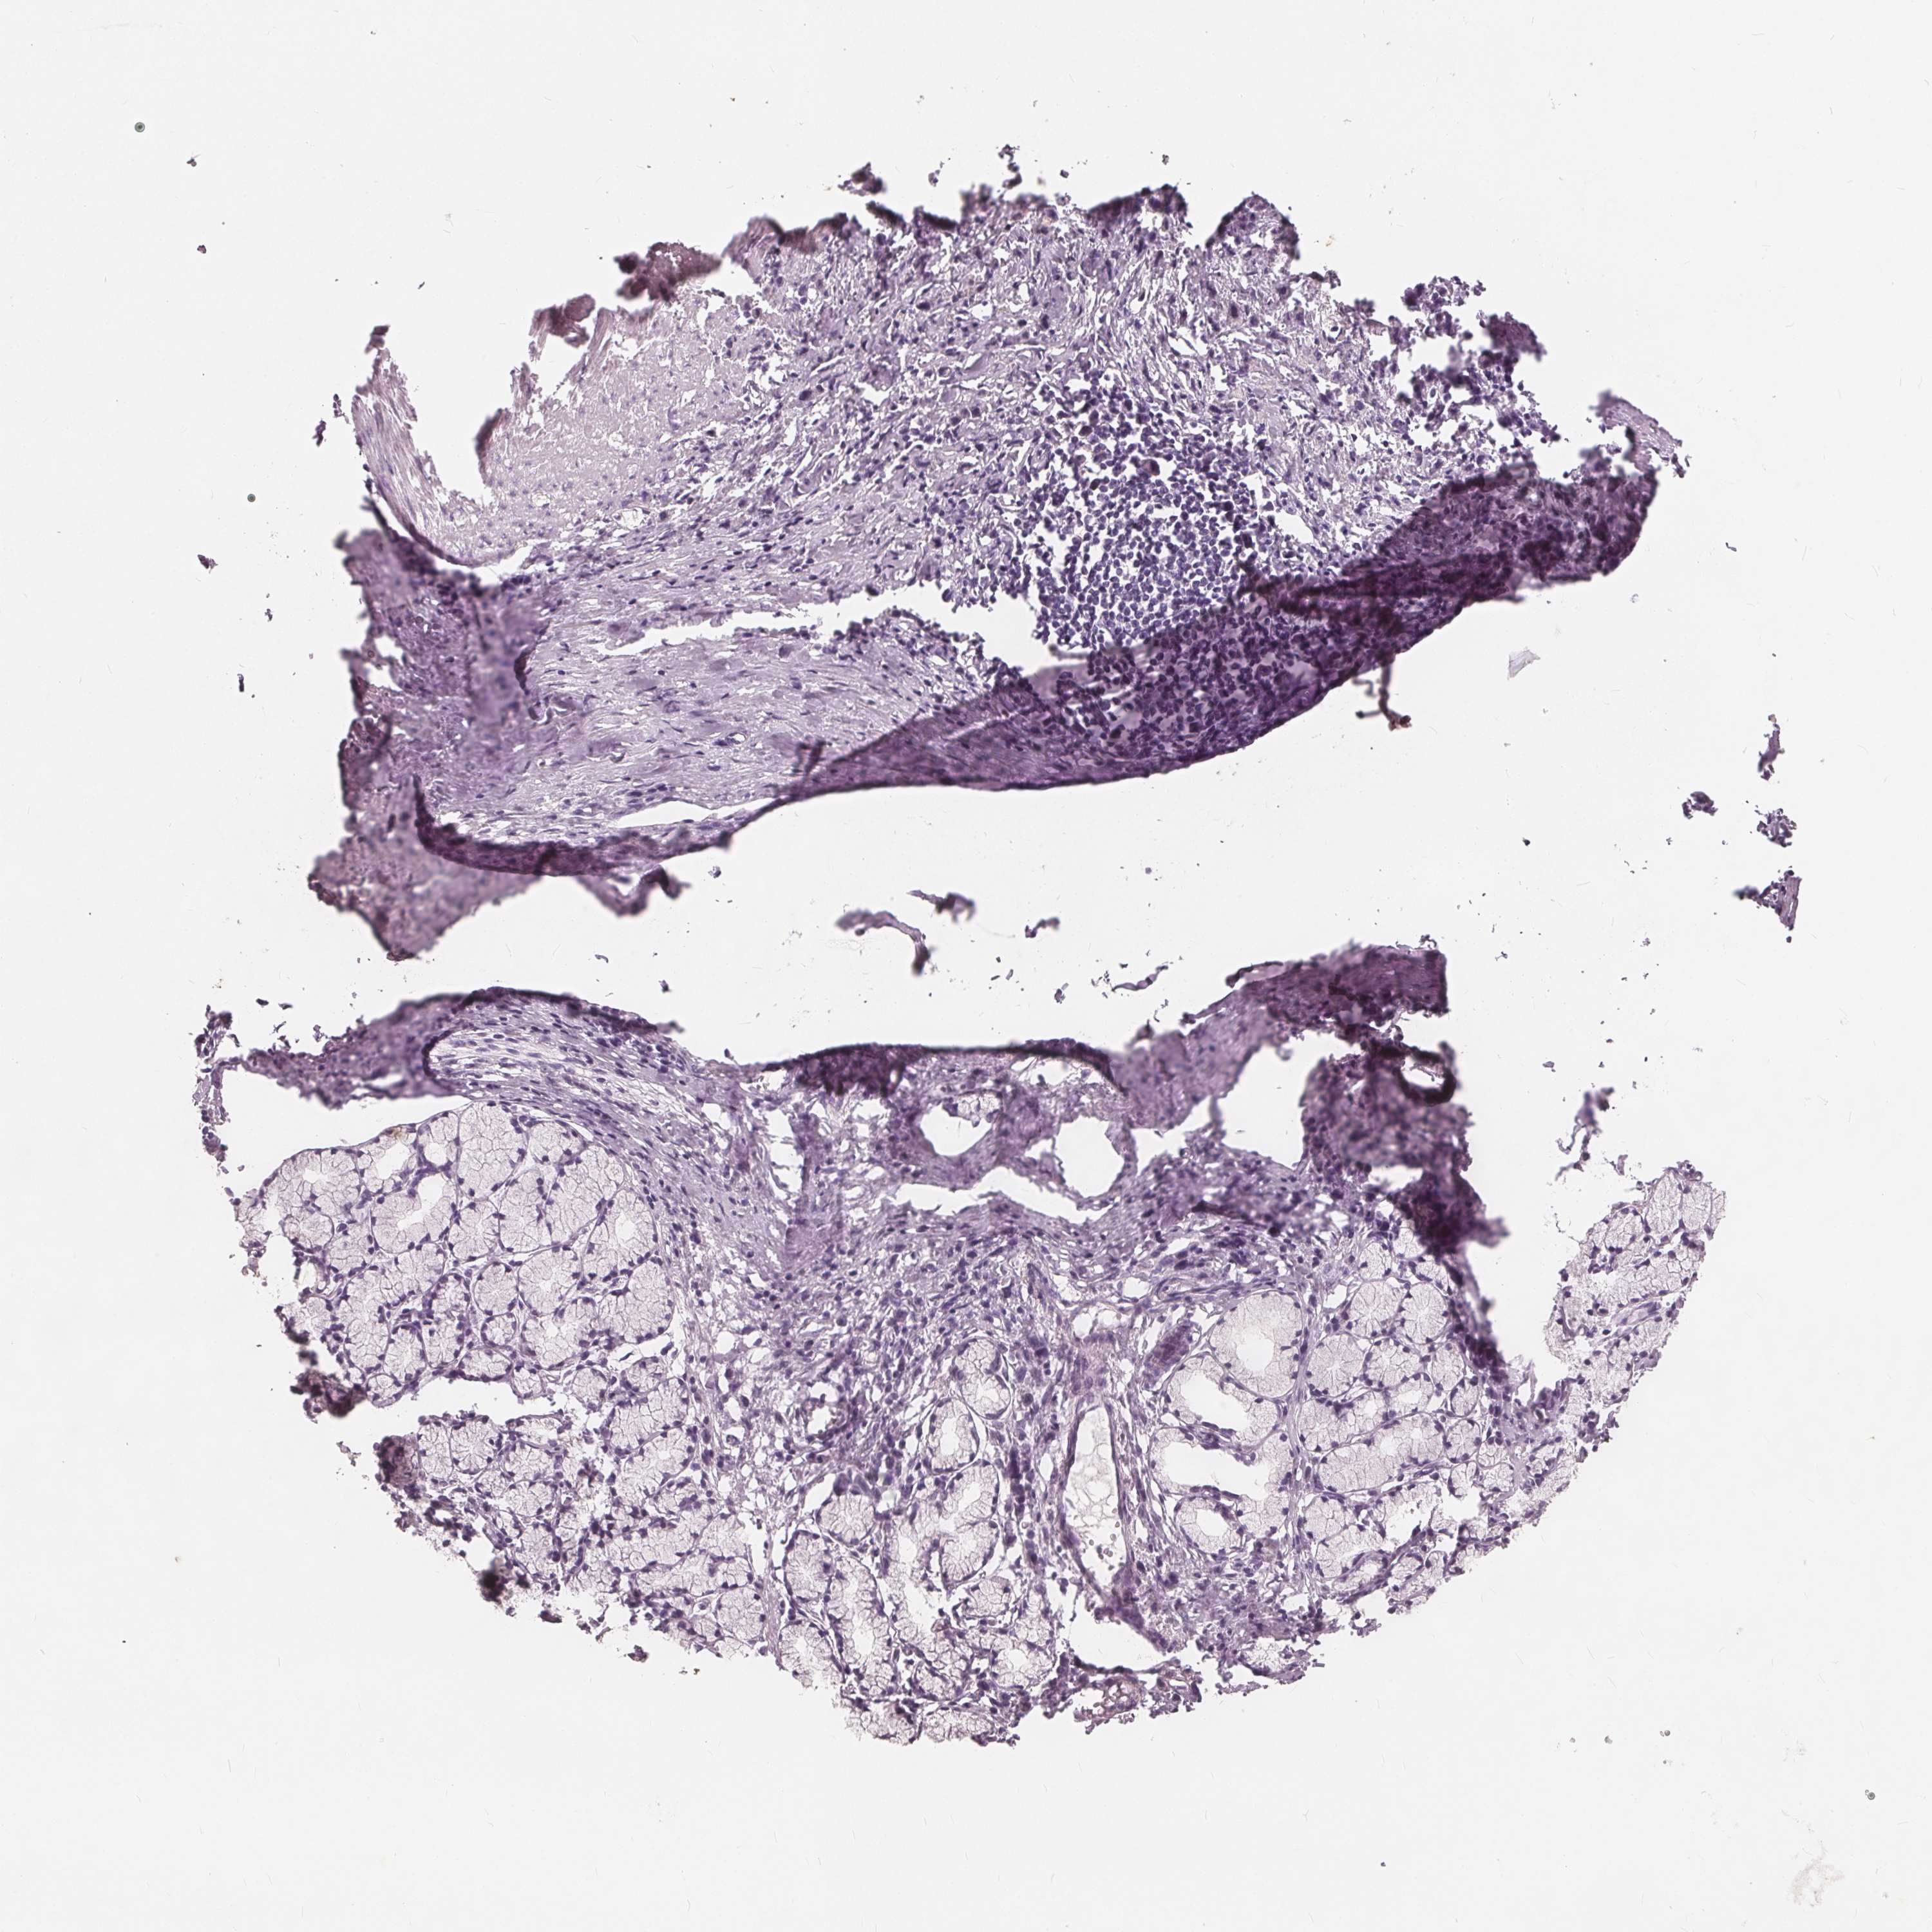

STOMACH CANCER - Protein expressioni

A mouse-over function shows sample information and annotation data. Click on an image to view it in a full screen mode. Samples can be filtered based on level of antibody staining by selecting one or several of the following categories: high, medium, low and not detected. The assay and annotation is described here.

Note that samples used for immunohistochemistry by the Human Protein Atlas do not correspond to samples in the TCGA dataset.

Antibody stainingi

Antibody staining in the annotated cell types in the current human tissue is reported as not detected, low, medium, or high, based on conventional immunohistochemistry profiling in selected tissues. This score is based on the combination of the staining intensity and fraction of stained cells.

Each image is clickable and will lead to virtual microscopy that enables deeper exploration of all samples and also displays staining intensity scores, fraction scores and subcellular localization as well as patient and tissue information for each sample.

Antibody HPA039486

Antibody HPA048186

Staining

High

Medium

Low

Not detected

Intensity

Strong

Moderate

Weak

Negative

Quantity

>75%

75%-25%

<25%

None

Location

Nuclear

Cytoplasmic/membranous

Cytoplasmic/membranous,nuclear

Adenocarcinoma, NOS